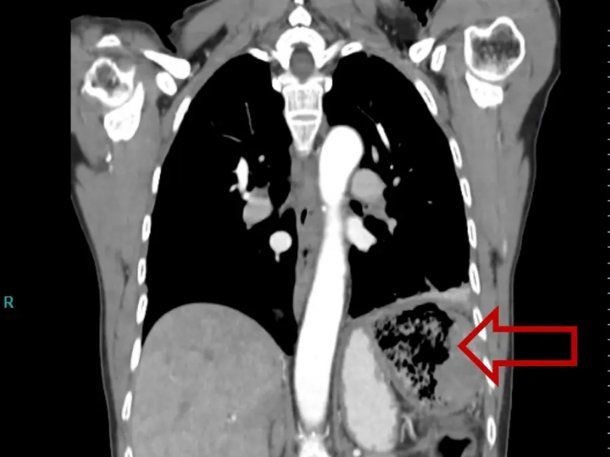

Alarmada por la aparición repentina de los síntomas, la paciente acudió al hospital, donde las ecografías revelaron una gran gasa en el abdomen. Los médicos creían que el polizón pegajoso se había quedado en su colon durante la operación dos décadas antes.